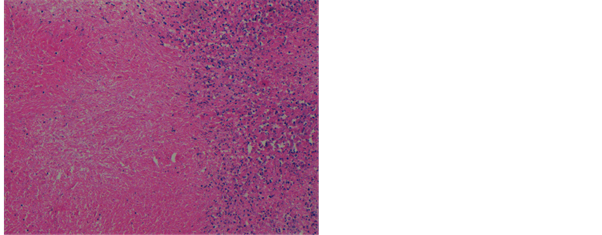

Then the tissue was processed by automatic tissue processor Microm GmbH cat. No.“813150” using different reagents (10% formalin, ethanol, xylene and paraffin wax). After this tissue is embedded in automatic Tissue Tek TEC model “TEC 5 EMJ-2” using molten paraffin wax. Paraffin embedded sections were prepared using microtome model “RM 2125 RT”. The H & E stain was performed on the slides to determine the histological diagnosis for selecting tissues and only the caseous or non-caseous granulomatous lymph nodes were selected (Figure 3). Slides were stained with ZN staining and fluorescent staining tech-

Figure 3. Photomicrograph of lymph node showing extensive early coagulative necrotic changes, 100×, H & E stain.